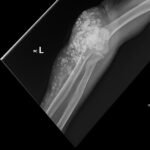

Calcinosis cutis is a condition in which calcium-phosphate salt deposits are formed in cutaneous and subcutaneous tissue. A subtype, metastatic calcinosis cutis, can occur in patients with disorders that cause hypercalcemia or hyperphosphatemia such as end stage renal disease. We present a case of a 67-year-old man with end-stage renal disease (ESRD) on dialysis who presented to the emergency department with a draining left elbow wound. On exam, he had irregular, firm nodules palpable in the subcutaneous tissue of both large and small joints. The presence of calcinosis cutis on imaging and lack of other findings suggesting infection led to outpatient wound care treatment. Recognizing the appearance of calcinosis cutis on imaging and conditions that present with calcinosis cutis is important for the emergency physician.